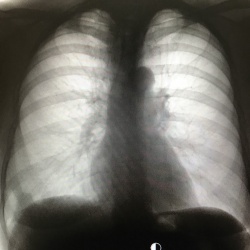

Женщина 55 лет. В апреле - мае 2017г перенесла радикальную мастэктомию ПМЖ по поводу инфильтрирующей карциномы правой молочной железы с метастазами в региональные л/у. Проходила курс...